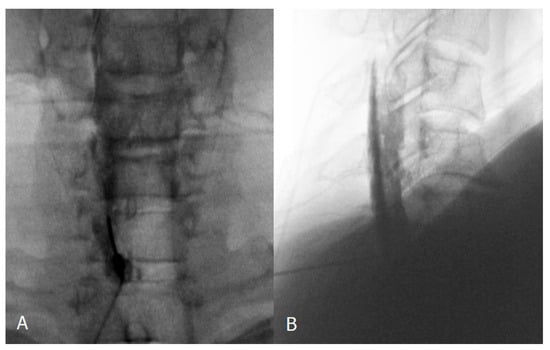

2.2. Injection Technique

2.3. Image and Data Analysis